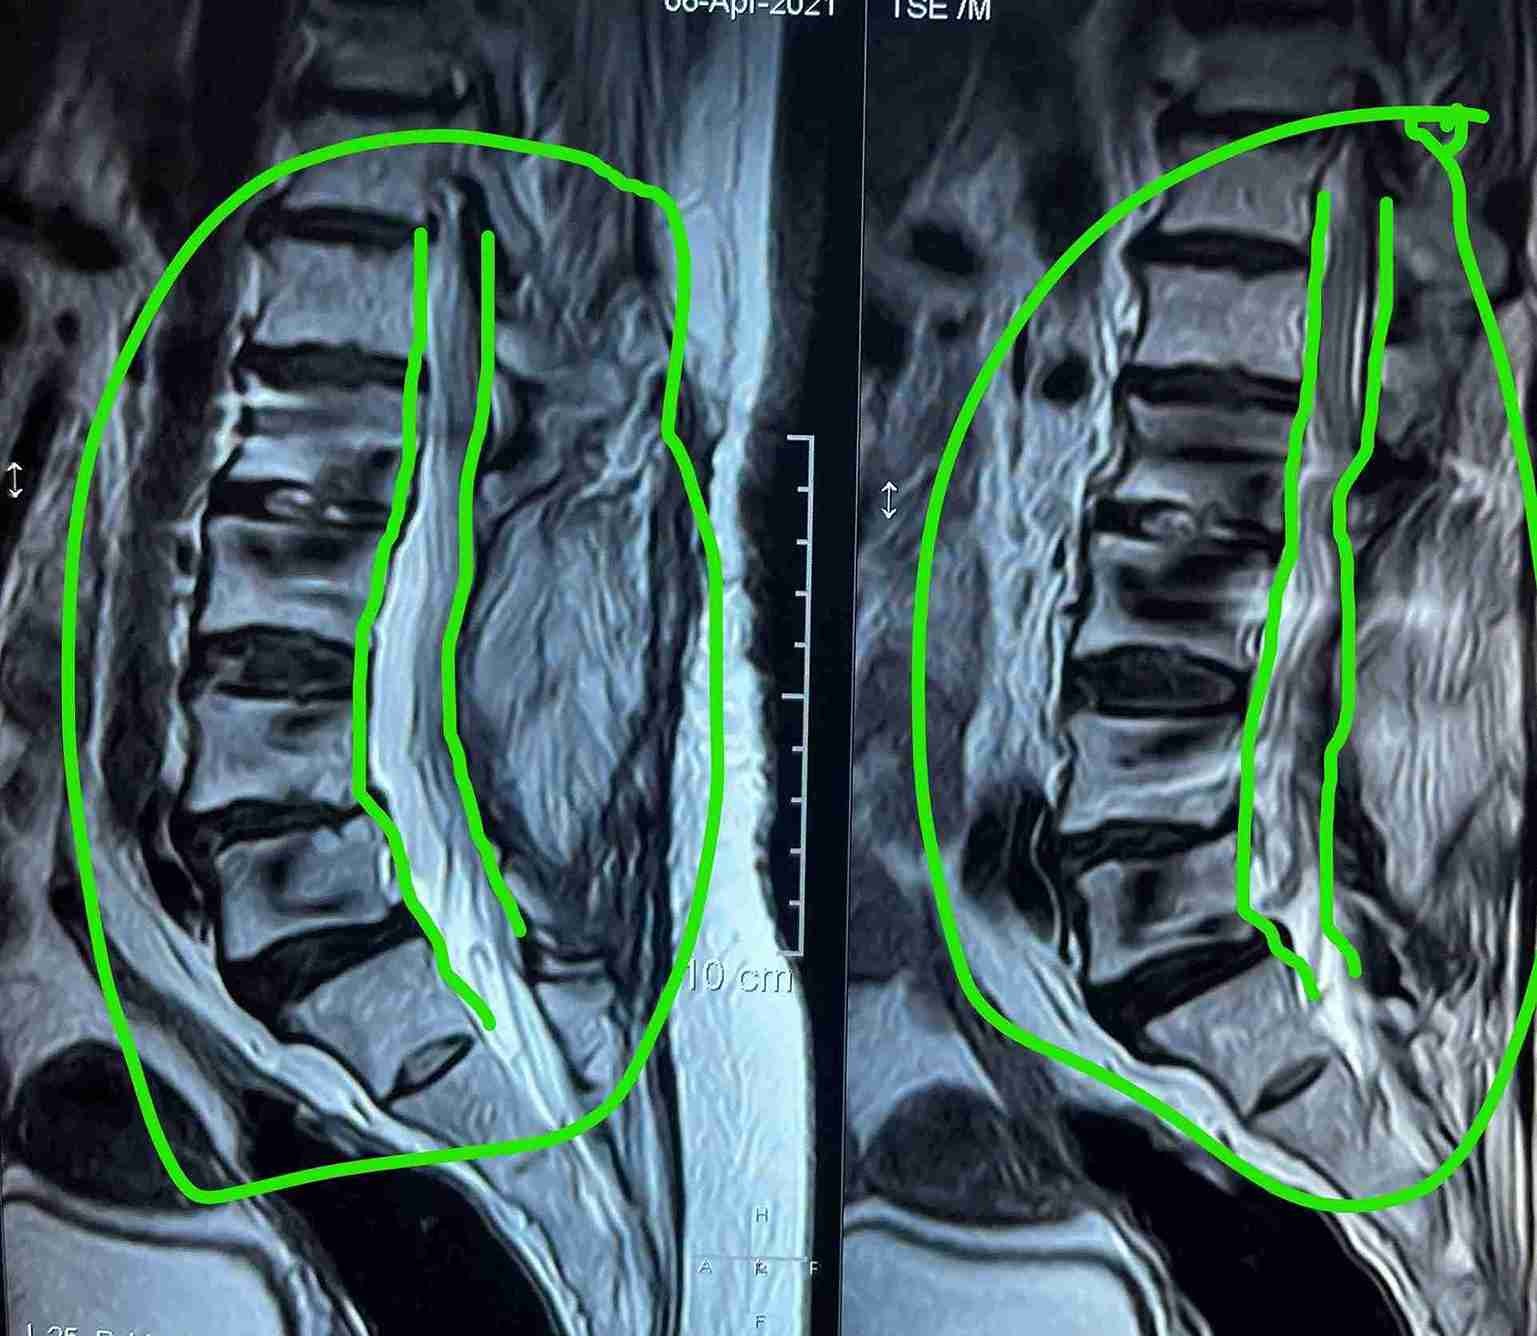

ضيق بالقناة العصبية القطنية مستويات متعددة مع تزحزح فقاري قبل وبعد الجراحة

multiple levels of lumbar nerve canal stenosis with spondylolisthesis before and after surgery

A successful surgery was performed to treat multi-level lumbar spinal stenosis accompanied by spondylolisthesis. This condition causes pressure on the nerves in the spinal column, leading to severe pain and difficulty in movement.